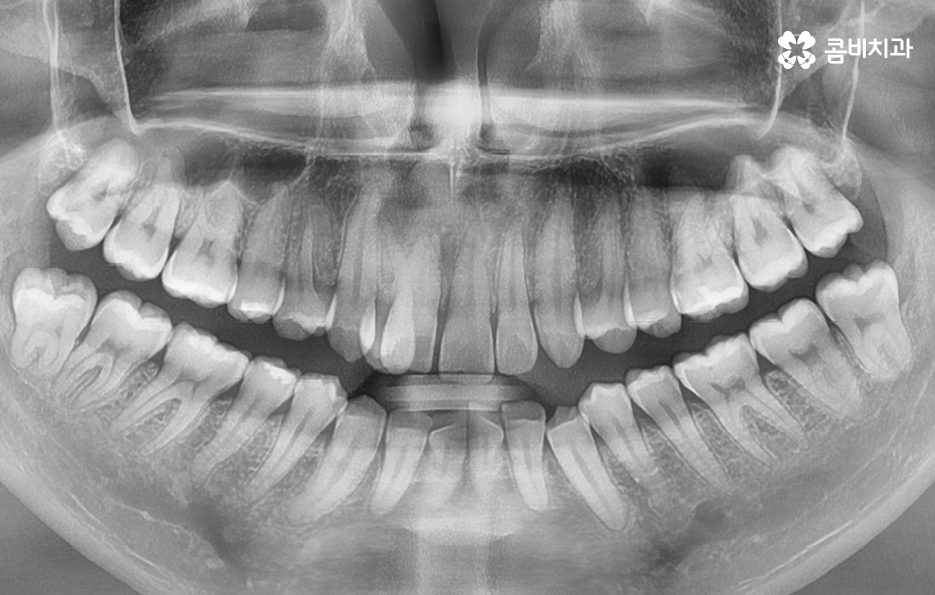

다만 덧니 교정 사례에서 발치교정 사례가 많은 이유는 턱뼈가 좁아서 치아가 덧니로 자란 경우가 많기 때문에 치열을 재배열하기 위해서는 치아가 움직일 수 있는 충분한 이동공간이 필요하기 때문에 공간 확보의 목적으로서 작은 어금니 양옆, 위아래 4개를 발치를 하는 발치교정법이 보편적으로 많이 활용되고 있으며 치아의 이동 공간을 확보하는 방법으로는 발치 교정법 외에도 악궁확장, 어금니 후방이동, 치간삭제와 같은 비발치적인 방법도 가능하기 때문에 치아를 얼마나 이동시켜야 할지에 따라서 치료법은 개인차가 발생되고 있어요

발치교정이 필요한지 여부에 대한 판단은 치아의 이동 공간이 얼마나 필요하고 확보해야 하는지에 따라 달라지는데 이러한 판단 근거는 단지 치열만을 두고 보는 것이 아니라 골격과 얼굴형을 종합적으로 고려한다는 점에서 정밀검진과 함께 풍부한 경험을 갖춘 교정 전문의와 잘 상의하여 결정하신다고 보시면 될 거예요